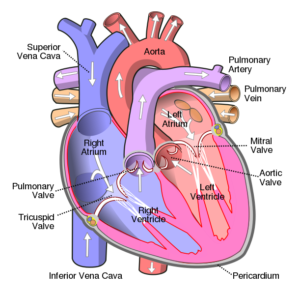

HEART:

The heartTrusted Source is the most important organ of the circulatory system, which helps deliver blood to the body. It works with the lungs to add oxygen to blood and pump this freshly oxygenated blood through the blood vessels and around the body.

The heart also has an electrical system within. Electrical impulses within the heart help ensure that it beats with a consistent rhythm and proper rate.

The heart rate increases when the body needs more blood, such as during intense exercise. It decreases during times of rest.

The heart has four chambers. The two upper chambers are called atria, and the two lower chambers are called ventricles.

Blood flows into the right atrium from the veins of the heart and body (except the lungs), then it flows into the right ventricle. From there, it flows into the pulmonary artery, which has branches that reach the lungs. The lungs then oxygenate the blood.

This oxygenated blood travels from the lungs, through pulmonary veins that lead back and join together, to the left atrium, and then through the left ventricle. From there, the heart pumps the blood through an artery that branches to distribute blood to itself and other body parts (except the lungs).

The heart has four valves that ensure that blood flows in the right direction. The heart valves are:the tricuspid valve

the pulmonary valve

the mitral valvethe aortic valve